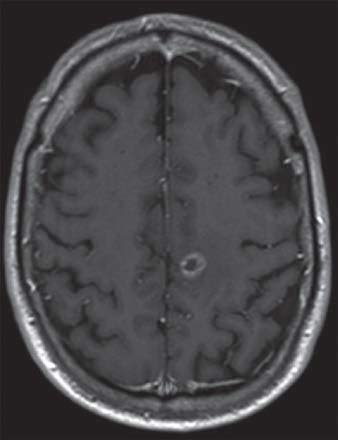

IRM d’un homme de 61 ans présentant des métastases dans l’hémisphère gauche du cerveau secondaire à un cancer du poumon

IRM d’une femme de 88 ans atteinte d’un méningiome de la fosse cérébrale postérieure

IRM d’un homme de 64 ans atteint d’un glioblastome